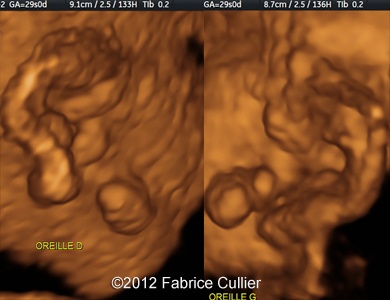

An amniocentesis was performed at 30 weeks (46 XY). On 2D and 3D ultrasound with multiplanar reconstruction and surface rendering with a voluson 730 US machine demonstrates bilateral pre-auricular tag with normal ears. 2D sagital views of the face at 29 weeks showed retrognatism with normal nose bones.

Image 1 : 2D-dimensional surface rendered view at 29 weeks demonstrates right and left ear dysplasia and preauricular tag.

1

Image 4, 5 : 3D surface rendered view at 29 weeks shows preauricular tags and ear dysplasia.

3

4